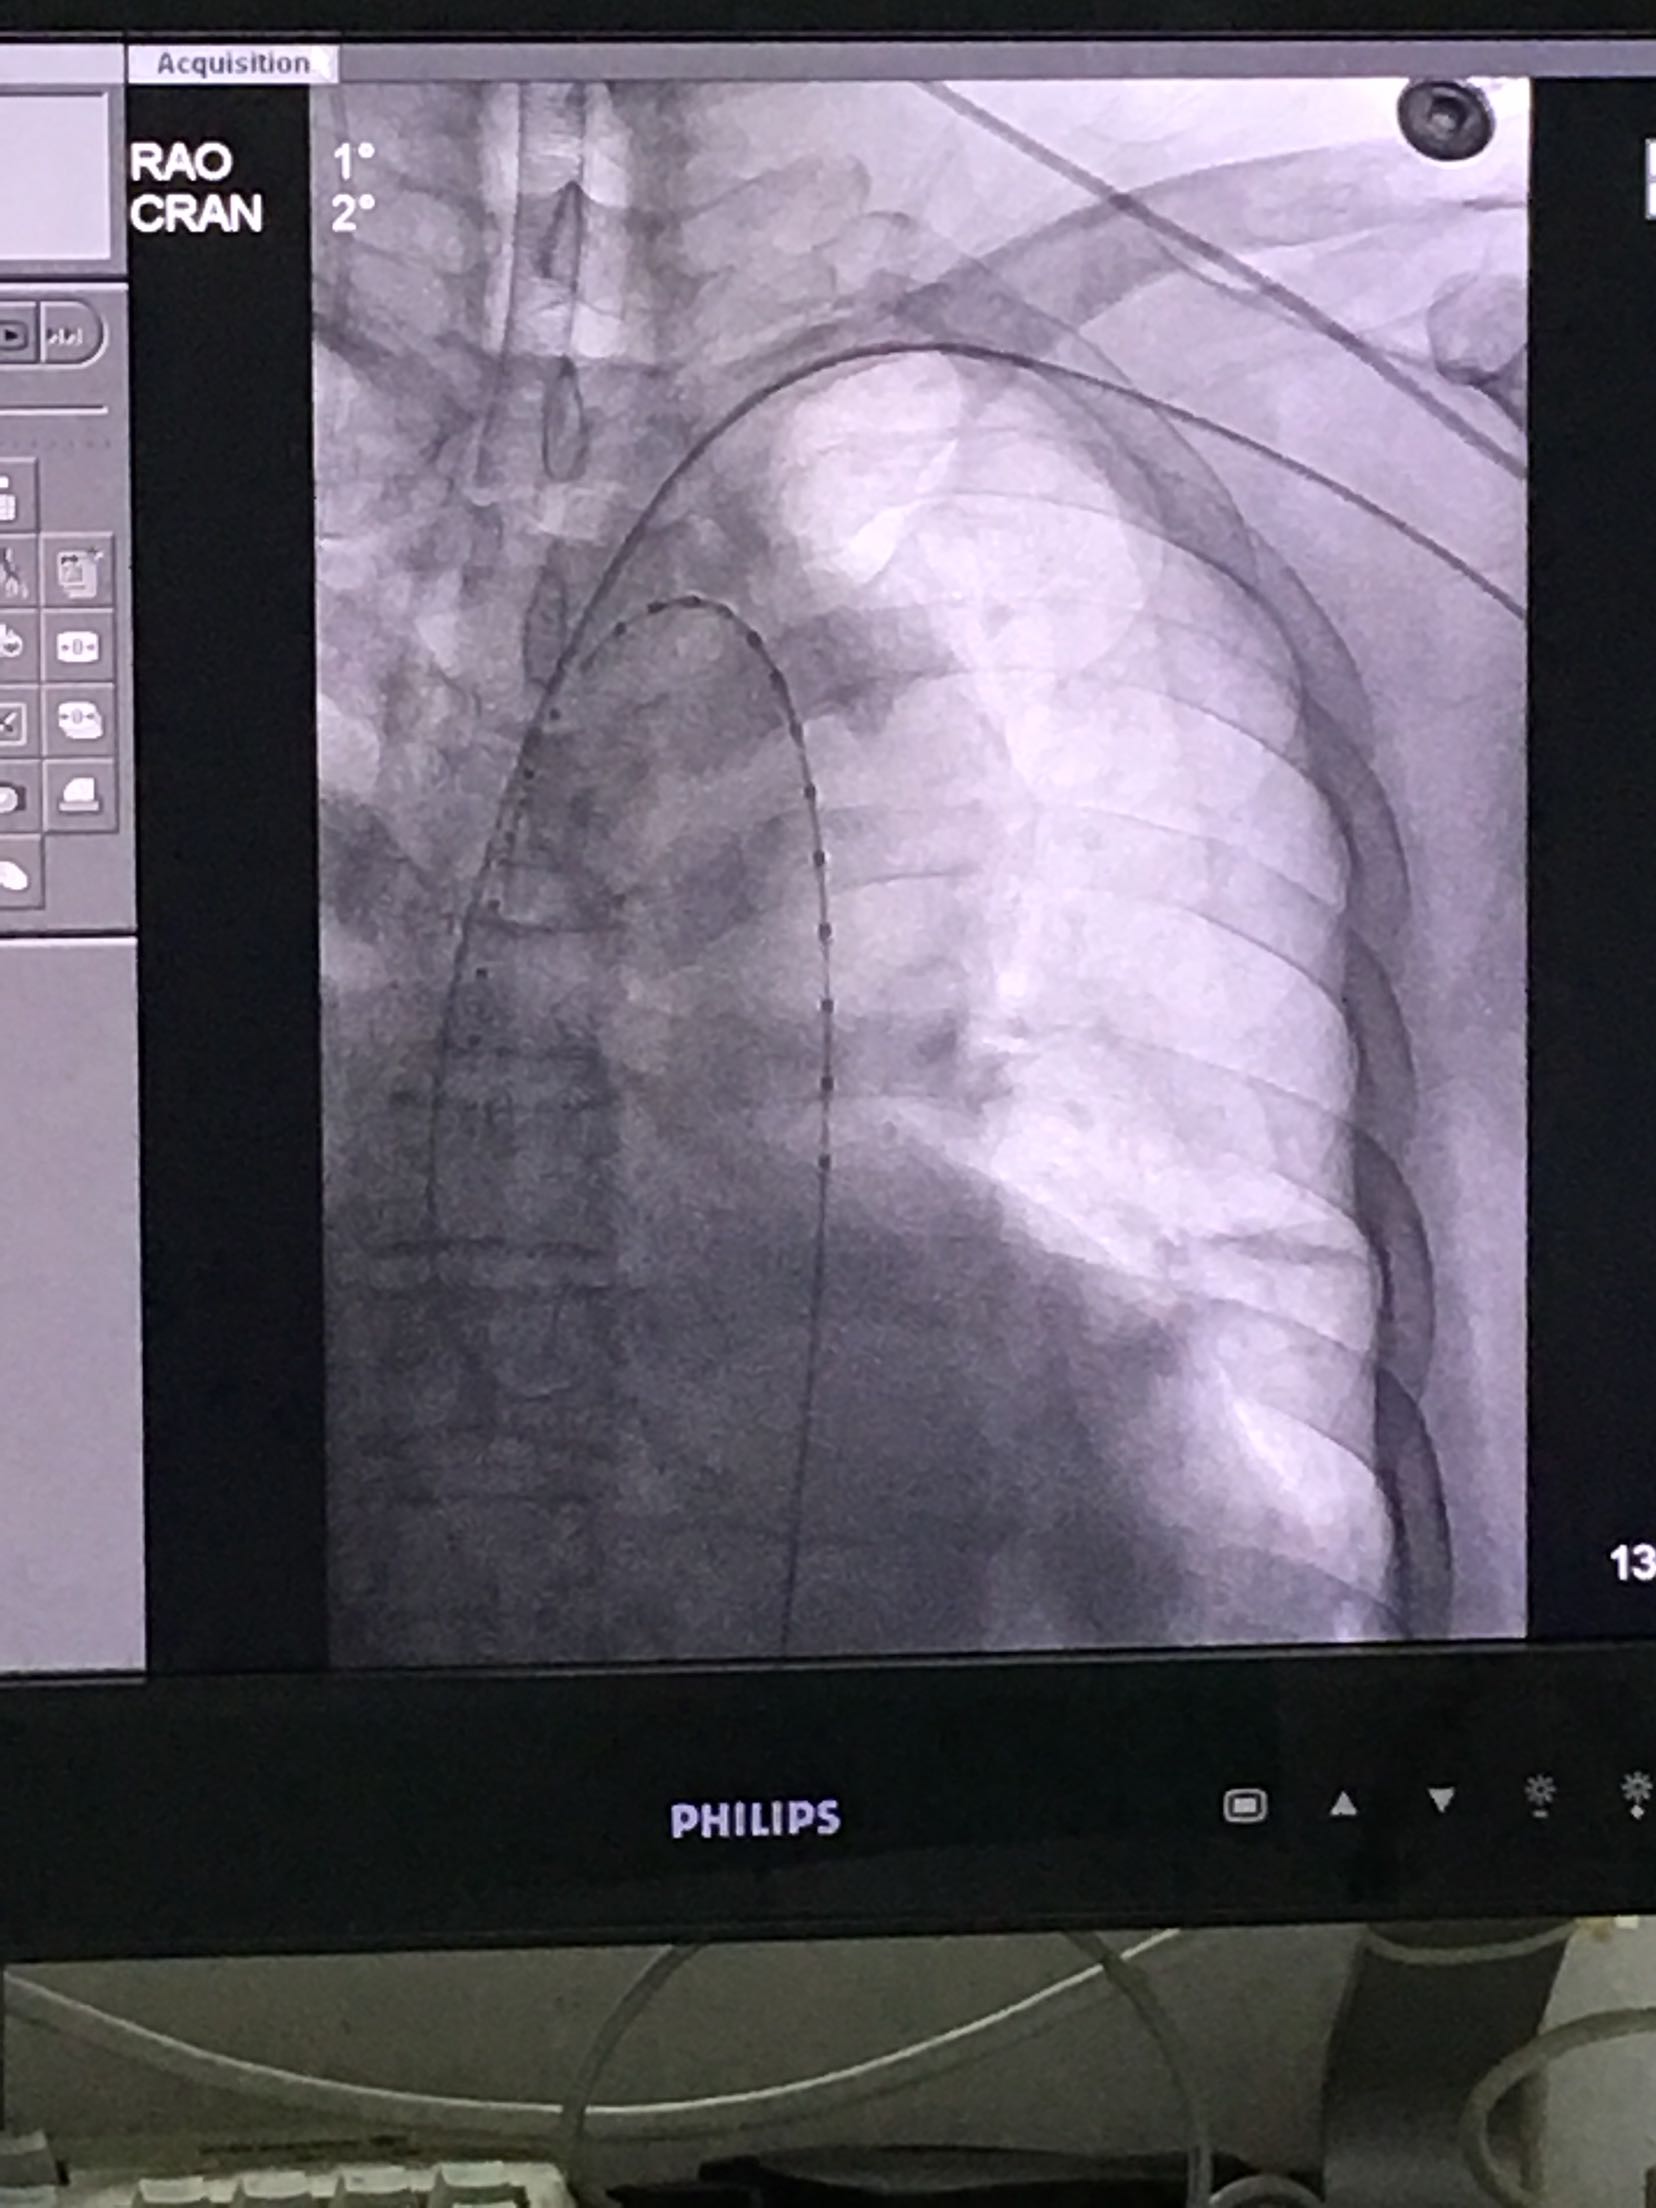

胸主动脉夹层1例行支架置入术

初步诊断: 1.主动脉夹层 2.高血压3级 极高危 硝普钠持续泵入控制血压,做好术前准备;密观生命体征,及时调整治疗方案。 治疗 介入室行胸主动脉夹层腔内隔断术

随访 讨论

术后一直静脉泵稳定血压,对症治疗,继续观察。